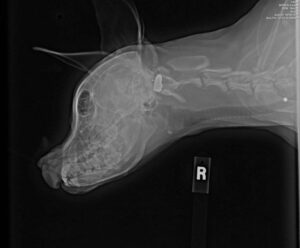

At just six months old, Bubbles was rescued by a dog shelter in Houston, Texas, where she received comprehensive examinations, including a CT scan that revealed the trajectory of the bullet. Unfortunately, the bullet caused extensive damage, leading to the loss of her eye and jaw, as well as inner ear injuries.